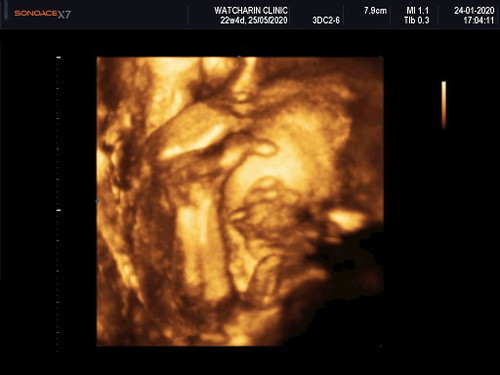

ตั้งครรภ์ได้24วีคมีภาวะน้ำตาลในเลือดสูง179 อย่างนี้จะเป้นอันตรายต่อทารกในครรภ์มั้ยคะ

เสี่ยงเรื่องเบาหวานขณะตั้งครรภ์ค่ะ คุมอาหารตามที่หมอสั่งนะคะ